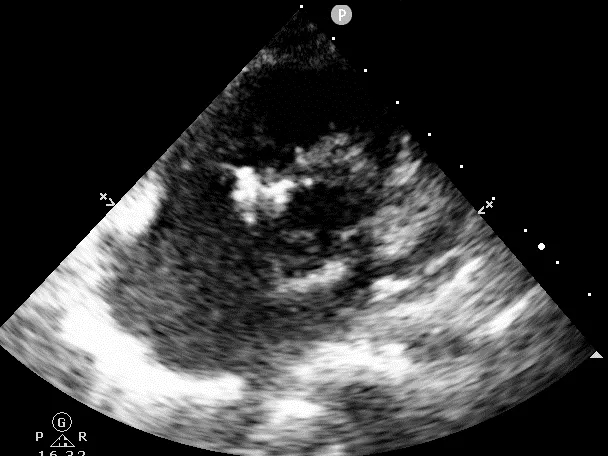

门诊心脏彩超提示:

超声多切面示:室间隔膜周部可见连续中断,局部不规则向右室膨出,呈“囊袋状”,断端回声增强,测缺口大小:左室面6.5mm、右室面2.5mm,隔瓣下残缘5mm,彩色血流示:室水平左向右分流,Vmax 473cm/s,Pgmax 89 mmHg。

各房室腔大小及大血管内径未见异常。各瓣膜厚度、弹性、开放幅度正常,彩色血流示:三尖瓣反流(少量),长度1.51cm、面积1.4cm2,容积1.0ml,Vmax 216cm/s,PGmax 16mmHg。据三尖瓣反流法估测肺动脉收缩压为28 mmHg;左室收缩功能正常,EF为74%。